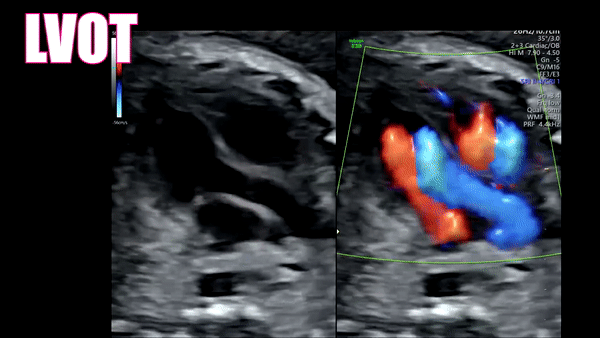

3rd: LVOT

As you focus on the left ventricle, you should see that the left ventricle is smooth walled. The LVOT comes off the left ventricle and points towards the fetal right shoulder. As you follow the LVOT off the left ventricle angle your transducer towards the fetal right shoulder to elongate the LVOT. You should see the mitral valve and the Aortic valve as you evaluate the LVOT.